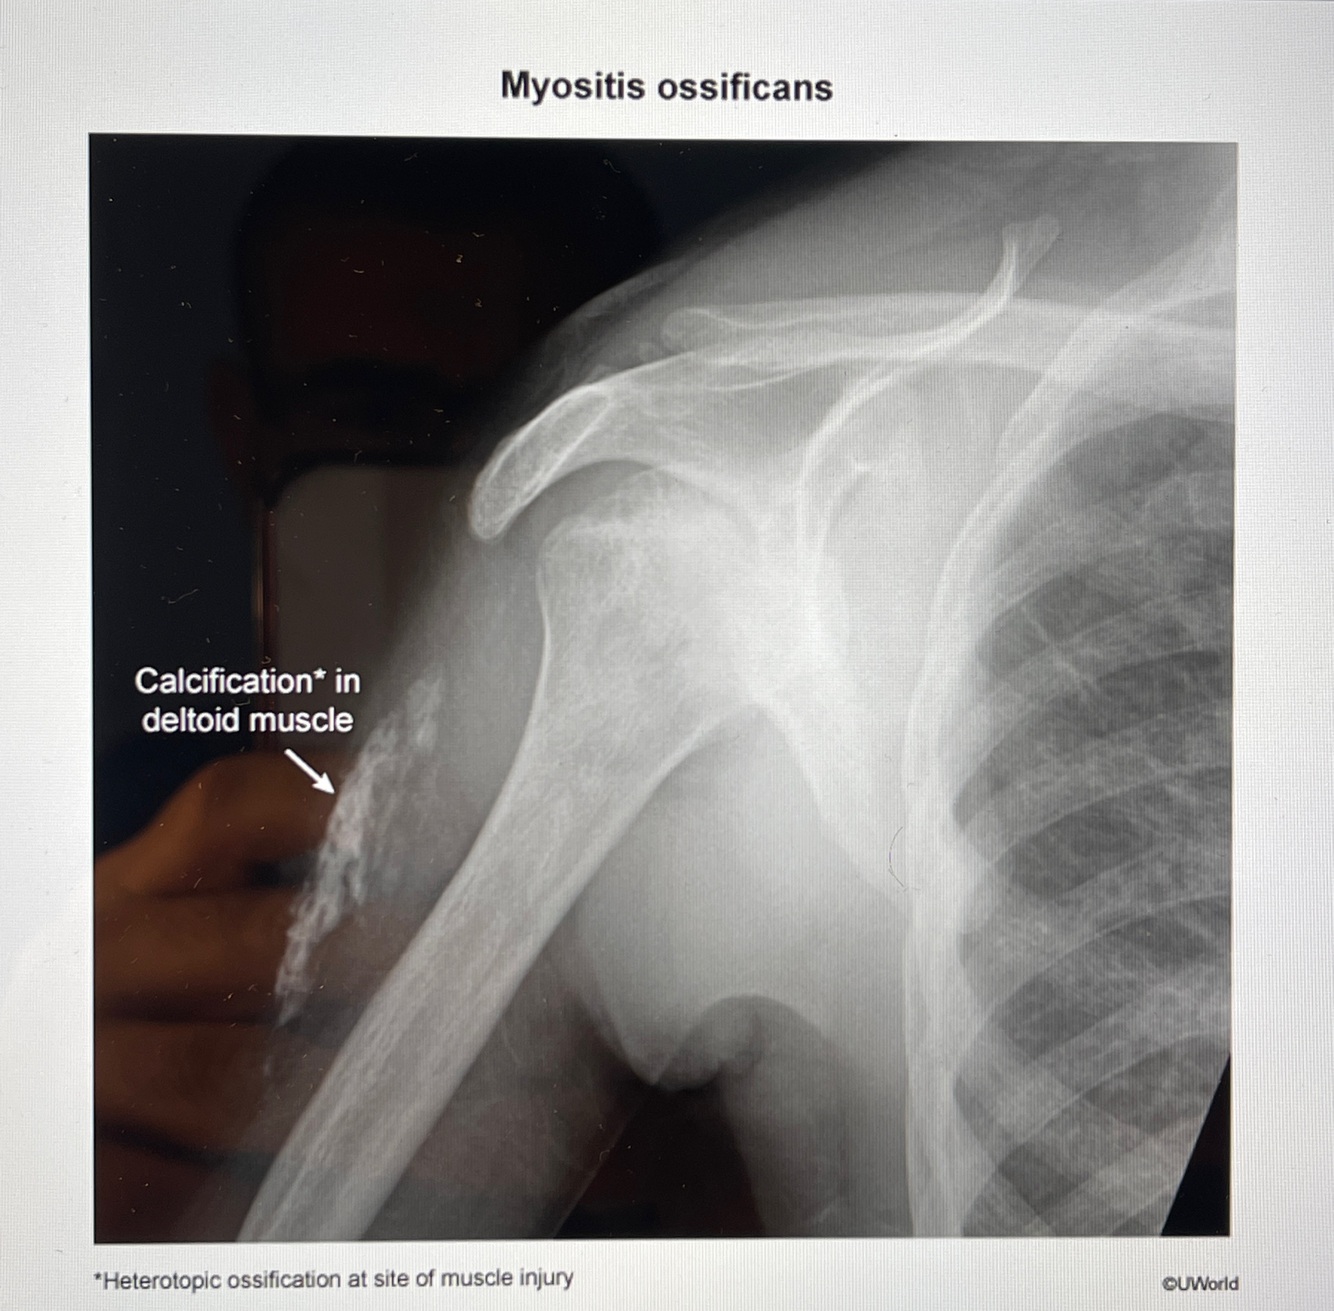

A

How well did you know this?